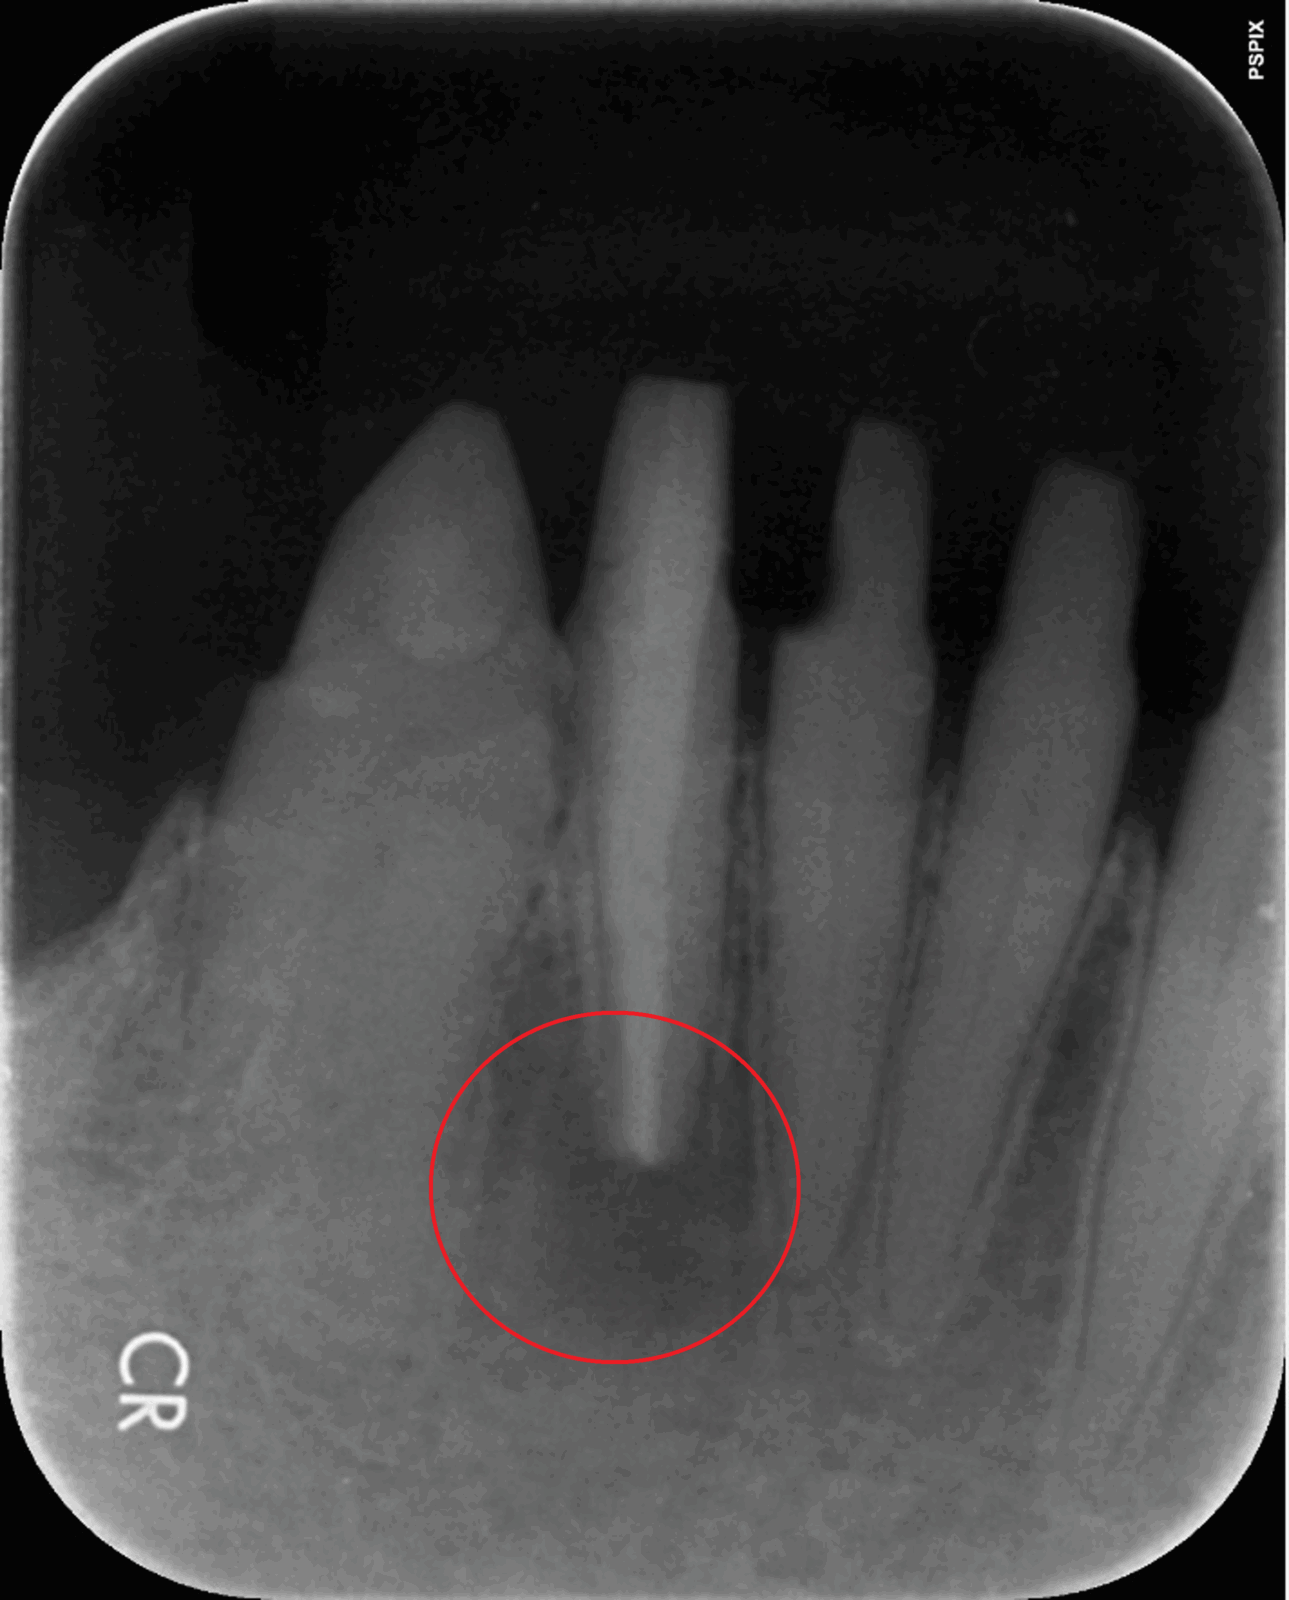

• 治療前

• 治療後

根の先端の炎症を治療する「歯根端切除術」

根の先端に膿が溜まる状況を「根尖病巣」と言います。この状態になると多くが「抜歯宣告」されます。しかし「歯根端切除術」という術式で、抜歯をせずに治療できる場合があります。

歯根端切除術では、歯茎の外側を外科的に切り開き、歯の根の先端ごと膿の袋を取り除きます。取り除いた後の空洞は血液で満たされ、時間の経過と共に再生した骨で埋められます。